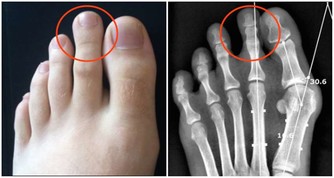

至陰:小腳趾外側指甲旁。艾灸可轉胎。